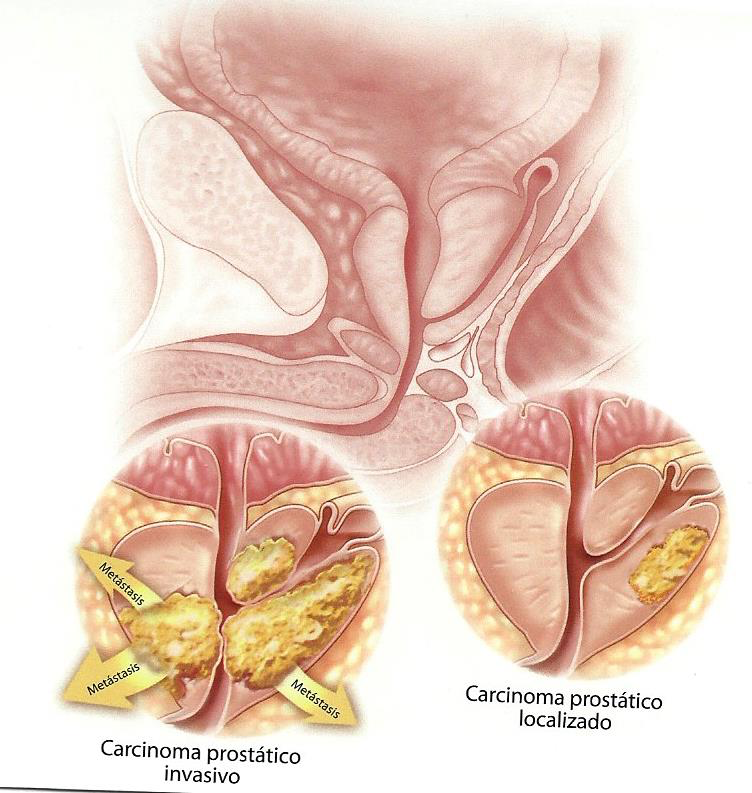

A partir de los cuarenta años, la próstata empieza a crecer. Este crecimiento puede ser benigno (hiperplasia) o maligno (cáncer). El cáncer de próstata es el cáncer más frecuente en el varón. Es fundamental realizar un diagnostico precoz ya que el cáncer de próstata si se diagnostica pronto puede curarse.